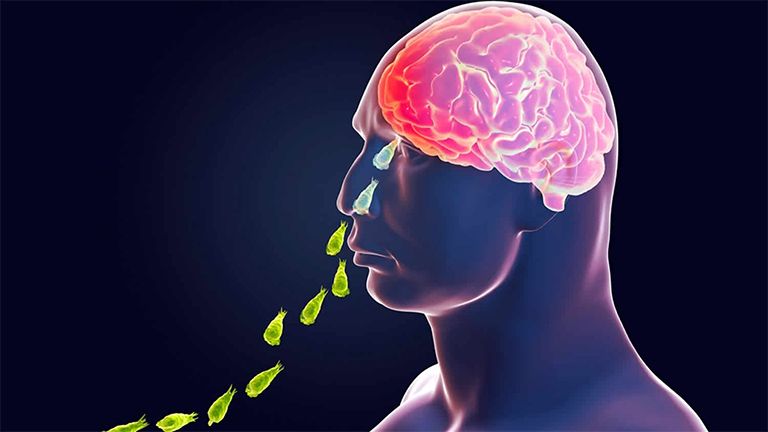

When the first cases were reported, the state machinery moved swiftly. Chlorination drives were launched across public ponds and household water sources, ensuring that the parasite had little chance to spread through contaminated water. Door-to-door awareness campaigns ensured that every household understood both the risks and the necessity of chlorinating their water sources. The state also issued strict guidelines to minimise the chances of amoeba entering the human body.

Kerala’s health department left no stone unturned, even importing Miltefosine, a critical drug not available in India, directly from Japan to save lives. At the same time, specialists in microbiology began conducting advanced studies to better understand the mode of transmission.

On the diagnostic front, Kerala once again distinguished itself. Detection centers were quickly established in medical college microbiology labs, and the Thiruvananthapuram State Public Health Lab was equipped with advanced facilities to identify the specific amoeba species causing the infection. While most labs in India can identify only three types of amoebae, the Thiruvananthapuram facility can identify five. Kozhikode, too, was provided with facilities for primary detection. Globally, only about 30 percent of patients with amoebic meningitis receive accurate diagnosis and treatment, with many countries lacking even a single lab. Kerala, however, has ensured that the most modern system in India operates right here.

The importance of early detection was underscored in a remarkable case that has now entered medical history. For the first time in the world, a patient confirmed to have both amoebic meningitis and Aspergillus flavus infection was brought back to life in Kerala. Timely diagnosis and intensive medical care ensured the patient’s survival, an achievement no other country has recorded.